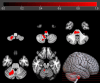

Results: sALS patients showed significant relative hypometabolism in bilateral fronto-temporo-occipital cortex and right insula as compared with FUS-ALS. After adjusting for age, the relative hypometabolism remained in the bilateral precentral gyrus and in the right middle and inferior temporal gyrus. As compared with HC, FUS patients displayed a significant relative hypermetabolism in the pontobulbar region and right cerebellar tonsil, dentate nucleus, and uvula, while sALS showed relative hypometabolism in bilateral frontal and occipital cortices and in left temporal and parietal regions.

Interpretation: Patients with FUS-ALS show relative preservation of motor cortex metabolism compared with those with sALS, possibly reflecting the prevalence of lower motor neuron impairment in their phenotype. Prospective studies are necessary to investigate the possible role of 2-[18F]FDG-PET as a biomarker to track disease spreading in clinical trials. ANN NEUROL 2025;97:1134-1143.